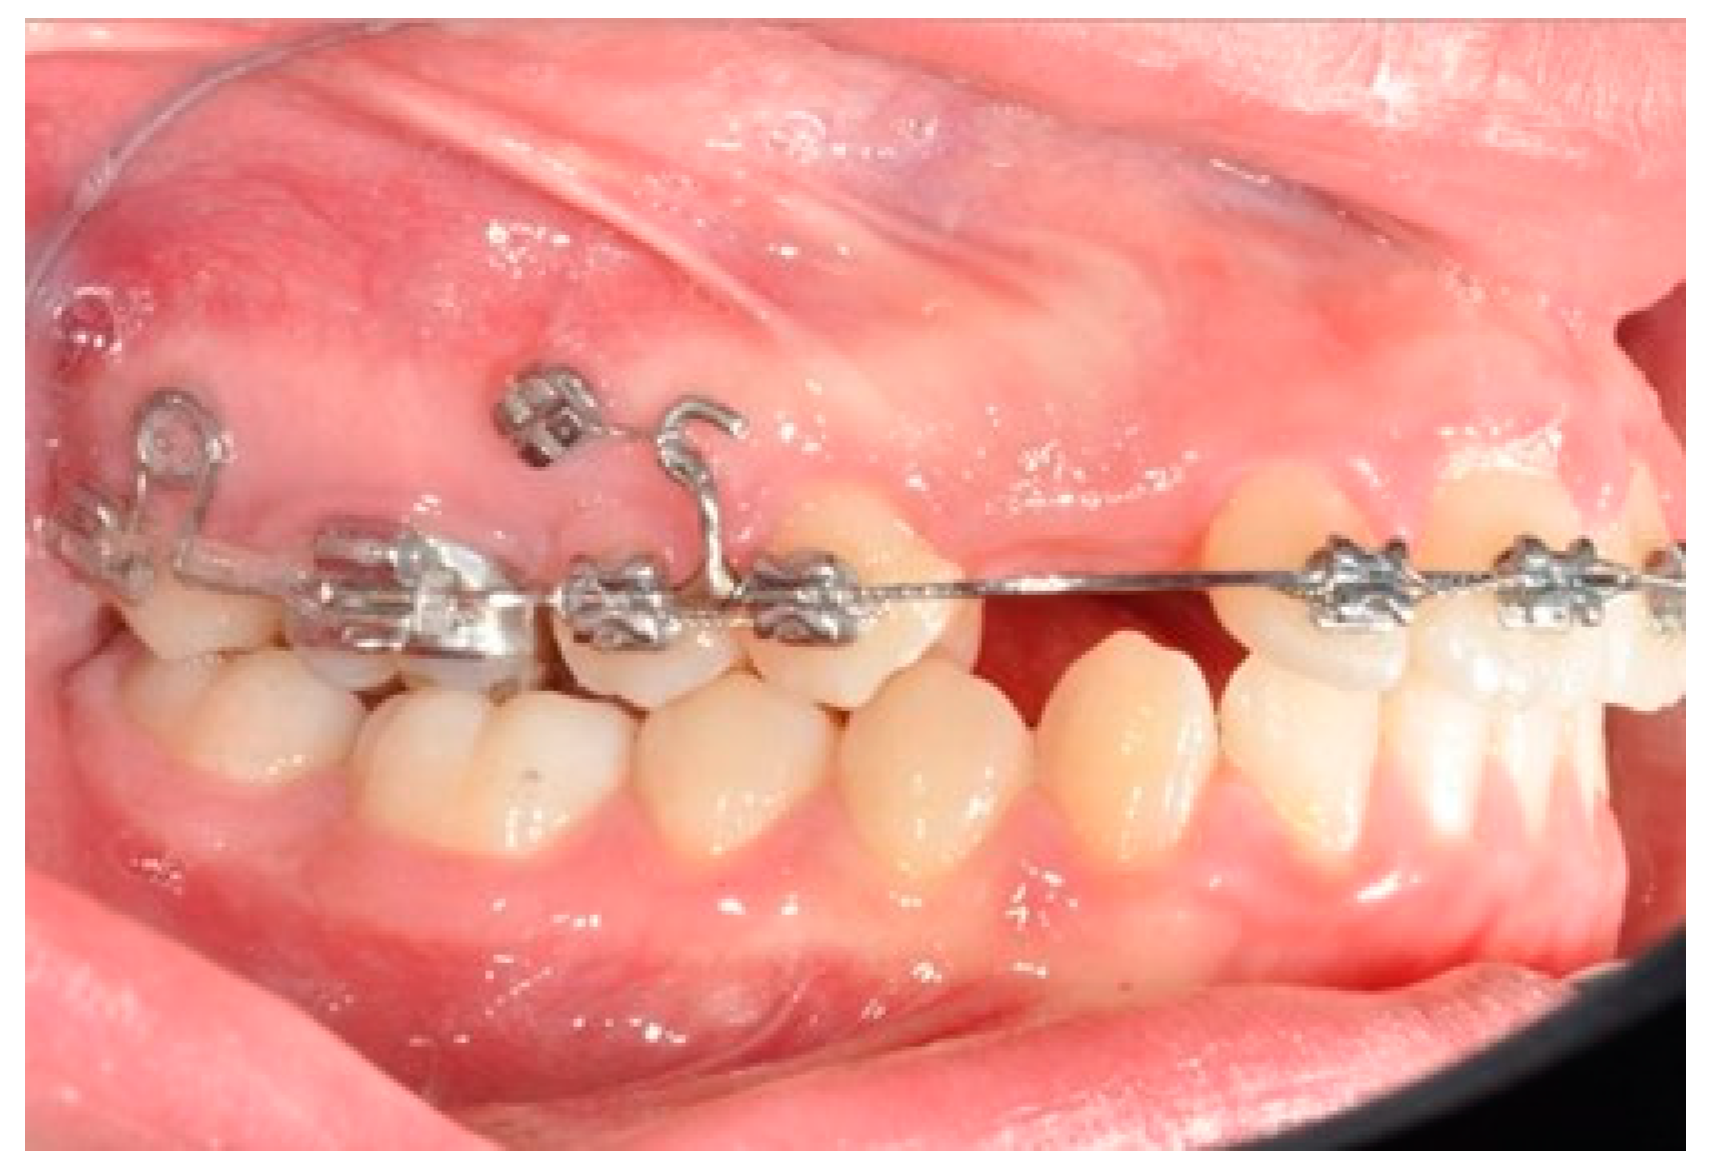

2.2. Molars’ and Premolars’ Distalization